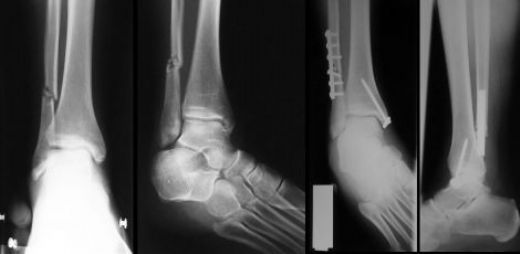

Kemik Onarımı

Kemik zarı, kemik yaralanmaları ve kırıkları sonrası onarım sürecinde de önemli bir görev üstlenir. Yaralanma durumunda, kemik zarındaki osteoblastlar ve osteoklastlar devreye girerek hasar gören bölgenin iyileşmesini sağlar.

• Osteoblastlar, yeni kemik dokusu oluştururken, osteoklastlar eski ve hasarlı kemik dokusunu parçalayarak yeni kemik oluşumuna zemin hazırlar.

• Kemik zarı, yaralanma sonrası doku iyileşmesini destekleyen büyüme faktörleri ve sitokinler üretir.